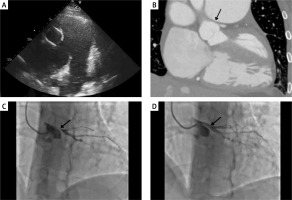

A 45-year-old female with pulmonary arterial hypertension (PAH) secondary to a congenital atrial septum defect was admitted to the cardiology department with diminished exercise tolerance (WHO class III) and chest pain. The patient was treated with sildenafil and ambrisentan. Blood investigations revealed NT-proBNP elevated to 2650 pg/ml (norm: 0–125 pg/ml). Echocardiography disclosed a large atrial septal defect with a bidirectional shunting, enlarged right atrium and ventricle with reduced systolic function, dilated main pulmonary artery (65 mm) and both pulmonary arteries, and mild tricuspid valve regurgitation (Figure 1 A). Right heart catheterisation revealed suprasystemic pulmonary pressures (systolic/diastolic/mean 104/41/62 with systemic blood pressure at 98/71/82 (mm Hg)), mean pulmonary artery pressure 62 mm Hg, pulmonary capillary wedge pressure 11 mm Hg, cardiac index of 1.7 l/min/m2, and pulmonary vascular resistance of 15.87 Wood units. The computed tomography angiography (CTA) showed compression of the left main (LM) coronary artery due to an aneurysm of the pulmonary trunk, resulting in significant stenosis of the LM (Figure 1 B). The Heart Team decided to perform percutaneous coronary intervention (PCI) during which a 5 × 20 mm drug-eluting stent was successfully implanted in the LM artery and in the proximal segment of the left anterior descending artery (Figures 1 C, D). Post-PCI, the patient experienced no recurrence of angina. Upon discharge, the patient was prescribed dual antiplatelet therapy (DAPT), spironolactone, β-blocker, sildenafil, and bosentan. One month later, during a control visit, the patient remained free from angina, but a 5-fold increase in aminotransaminases was observed, leading to the replacement of bosentan with macitentan. The patient declined treprostinil therapy. Despite the increased risk of bleeding in patients with Eisenmenger syndrome [1], no complications of DAPT were observed. The appropriate management of patients with extrinsic LM compression secondary to pulmonary hypertension remains challenging. Among patients with low to moderate risk for coronary artery disease, CTA emerges as a suitable, non-invasive modality for the preliminary assessment. Contemporary evidence indicates that PCI facilitates long-term symptom improvement and is safe especially in cohorts with high surgical risk [2]. Galiè et al. reported that out of 45 patients treated with PCI for extrinsic LM compression, 41 experienced complete symptom relief [3].

Figure 1

A – transthoracic echocardiography, aneurysm of the pulmonary trunk, and dilated pulmonary arteries, B – computed tomography, compression of the left main (LM) coronary artery due to an aneurysm of pulmonary trunk, C – coronary angiogram (CA), compression of the LM accompanied by restricted blood flow to the left anterior descending artery (LAD) and to the circumflex artery (Cx), D – CA, LM after percutaneous coronary intervention